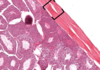

Pars nervosa of pituitary consists of neuropil, pituicytes, endothelial cells, fenestrated capillaries, Herring bodies

Pars nervosa: neuropil is wispy material, most nuclei belong to pituicytes, some endothelial cells near RBC, fenestrated capillaries, identifying feature: pink blob called Herring bodies

Pituitary - Pars nervosa: fenestrated capillary, neuropil, Herring body

Pars nervosa: pituicytes, herring bodies

Pituicyte of pars nervosa

Pars nervosa of pituitary gland